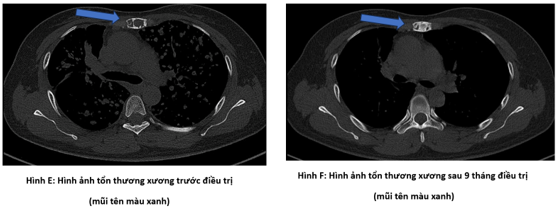

Bệnh nhân đi khám tại bệnh viện Bạch Mai được chụp cắt lớp vi tính lồng ngực phát hiện nhu mô thùy trên có khối đặc kích thước 40 x 35mm, các nốt đặc đường kính <12mm lan tỏa nhu mô hai phổi, ổ tiêu xương ức kích thước 31 x 13mm.

Hình 2: Hình ảnh tổn thương xương trước điều trị: ổ tiêu xương ức kích thước 31 x 13 mm (mũi tên màu đỏ)

Hình 4: Hình ảnh sau các đợt điều trị:  Các tổn thương của xương (không thay đổi số lượng và kích thước sau các đợt điều trị).